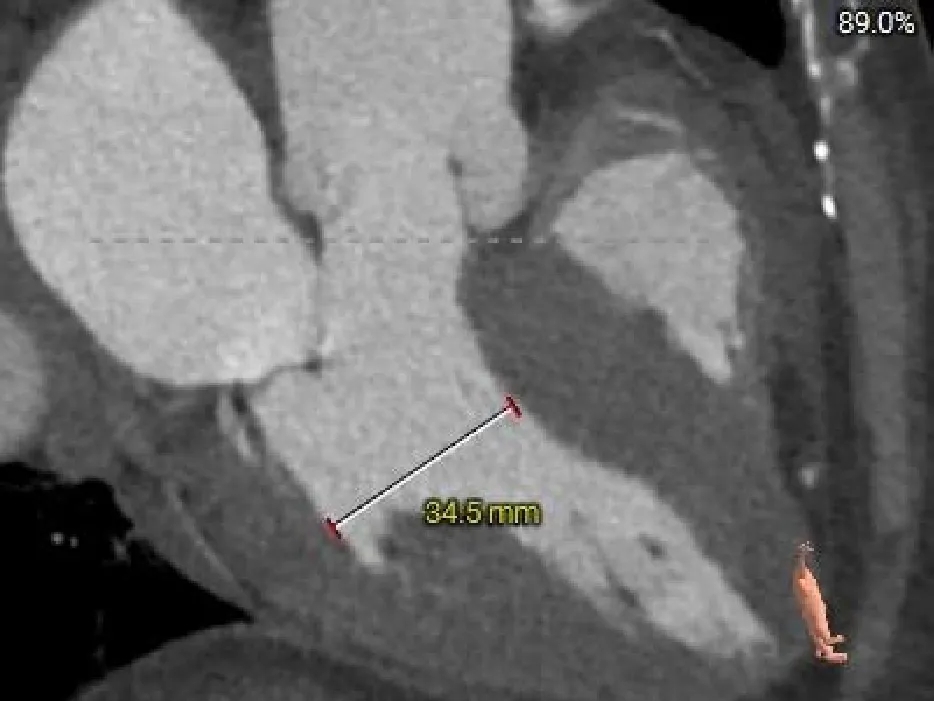

CASE Ⅱ

患者基本情况

基础信息:61岁,男性。

术前CT分析

主动脉根部测量

Annulus

25.9mm

LVOT

29mm

SOV

37.4*34.1*35.3mm

STJ

33.9mm

AAO

38.4mm

心脏角度

49°

-

纯反流三叶瓣,瓣环内径25.9mm

流出道敞口型

瓣叶轻微增厚、无钙化

瓦氏窦、STJ、升主内径可